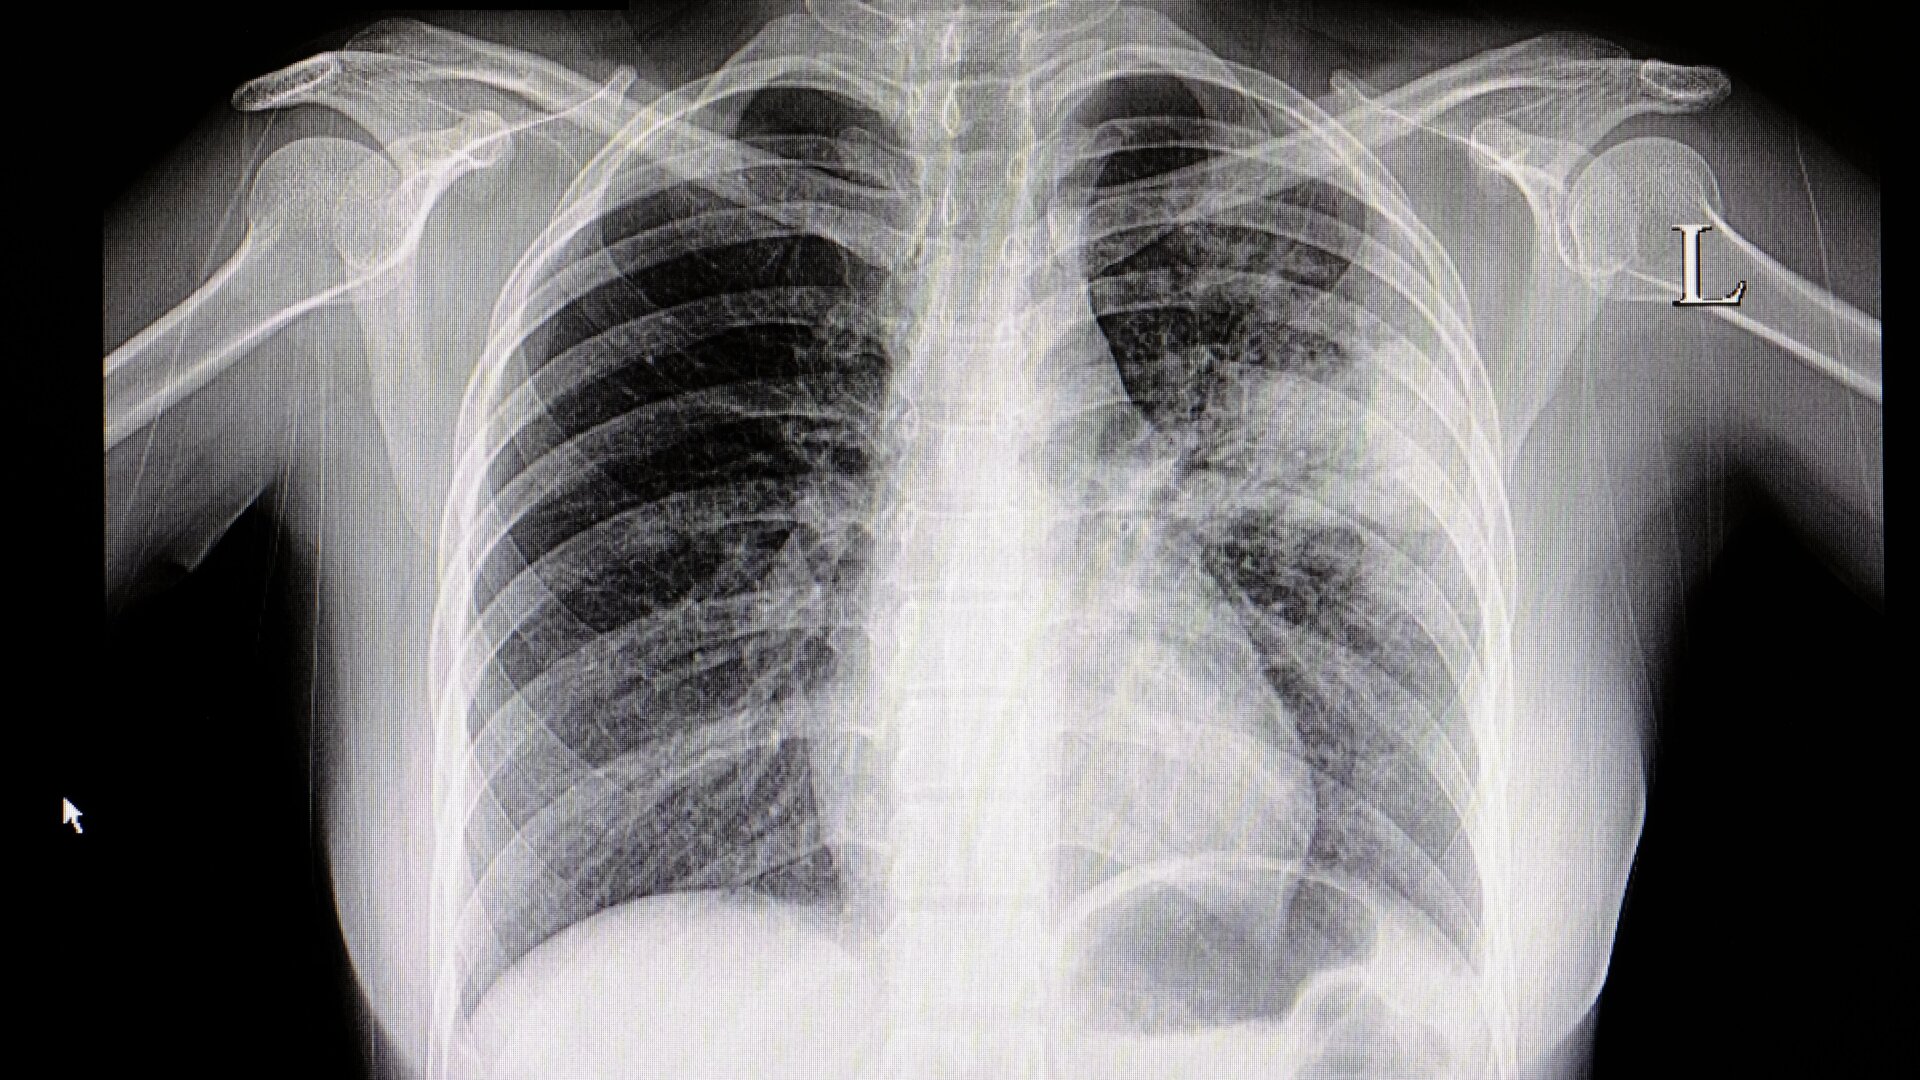

Un aumento inusual de enfermedades respiratorias ha estado azotando a China en los últimos meses, con un aumento de casos de neumonía que afecta a los niños en particular. A pesar de algunos Aunque hubo confusión temprana, los funcionarios de salud locales dicen que estos casos no están siendo causados por un germen nuevo. En cambio, es probable que el aumento esté relacionado a una combinación de enfermedades respiratorias conocidas, como la influenza y el VSR, que están afectando más de lo normal debido a la reducción de la inmunidad de la población en el área.

Las noticias sobre el extraño grupo se difundieron ampliamente por primera vez la semana pasada, luego de los informes de los medios locales compartidos en ProMED, un sistema de vigilancia basado en correo electrónico de eventos de salud organizados por la Sociedad Internacional de Enfermedades Infecciosas en 21 de noviembre. La alerta se refirió específicamente a los casos como una posible epidemia de neumonía (inflamación pulmonar ) no diagnosticada entre niños que viven en Beijing, Liaoning, y otras partes del norte de China. En algunas áreas, los hospitales de niños supuestamente estaban abrumados con casos.

Sin embargo, dos días después de la alerta de ProMED, la Organización Mundial de la Salud emitió su propia aclaración. declaración en el grupo. La OMS había notado por primera vez un posible aumento de casos de enfermedades respiratorias en el área que se remontaba a mediados de octubre de 2022. basado en los sistemas de vigilancia chinos. Una semana antes de la alerta, la Comisión Nacional de Salud de China informó sobre el grupo y los expertos atribuyeron el aumento. al levantamiento de las restricciones relacionadas con el covid y al resurgimiento mayor de lo habitual de varias enfermedades conocidas este invierno, incluida la gripe, el VSR y el covid-19 , y las bacterias Micoplasma neumoniae.

La OMS también habría celebrado una teleconferencia con las autoridades sanitarias chinas el 23 de noviembre, durante la cual los funcionarios compartieron datos sobre los brotes. Según la agencia de salud pública, los funcionarios no han detectado ningún patógeno inusual o novedoso, ni presentaciones clínicas inusuales, entre estos casos. Según se informa, el aumento no ha causado que los hospitales en general se sobrecarguen con los pacientes.